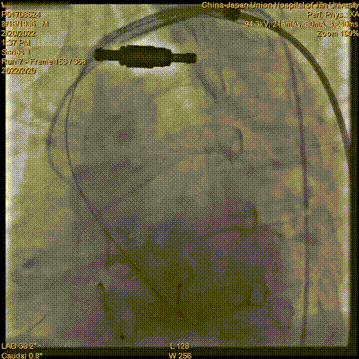

22mmTaurusAtlas球囊预扩张

输送系统过弓、过瓣